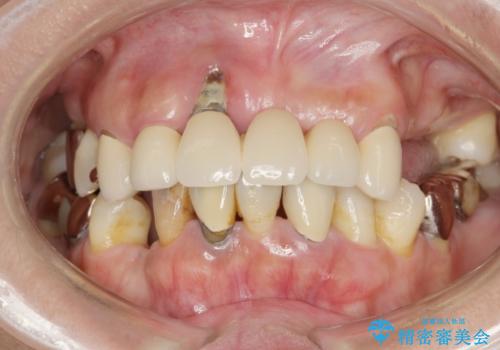

[20代男性] インプラント 失った歯の治療

![[20代男性] インプラント 失った歯の治療の症例 治療前](https://seimitsushinbi.jp/wp/wp-content/uploads/2019/11/IMG_0002-6-500x350.jpg?v=1574736384)